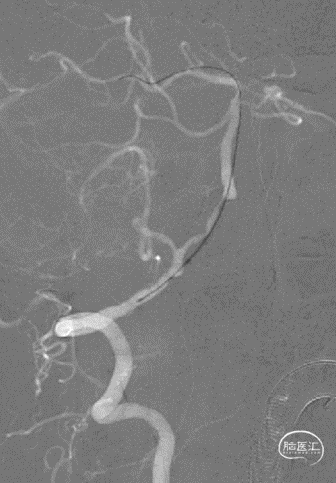

术前造影:

左椎动脉+左颈动脉造影:

右椎动脉造影:

右颈动脉造影:

右椎动脉动脉正侧位:

病变情况分析:右桡动脉穿刺,置6F桡动脉鞘管,5F多功能导管在泥鳅导丝辅助下脑血管造影提示:右椎动脉V4段重度狭窄(约90%)。